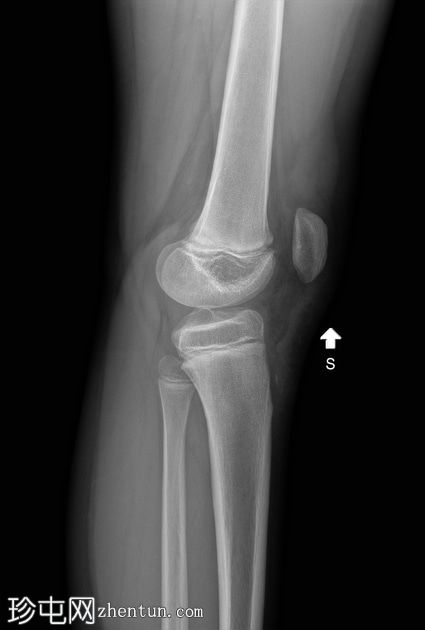

正位 -

负重位

髌骨下极可见一小块薄骨碎片,伴有髌骨高位,Insall-Salvati比值为1.5(V.N. 0.8 - 1.2)。膝前可见软组织肿胀。左膝正常。